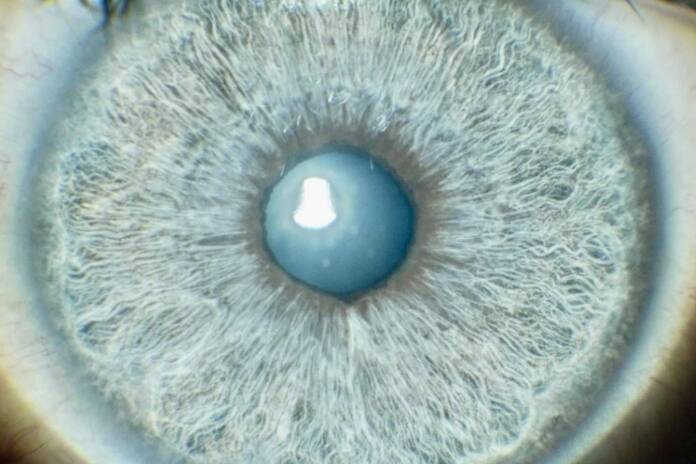

El cambio del color de ojos mediante láser es una innovadora opción oftalmológica que ha despertado un interés creciente. También conocida como iridoplastia láser, el cambio color ojos láser consiste en una técnica avanzada que altera la tonalidad natural de los ojos.

Esta modificación segura y eficaz de la pigmentación ocular se lleva a cabo en la clínica Eyecos, dando respuesta a todo tipo de necesidades. Y es que, más allá de la cuestión estética, llegan muchos pacientes motivados por realizar esta transformación con distintos fines profesionales, sentimentales y psicosociales.